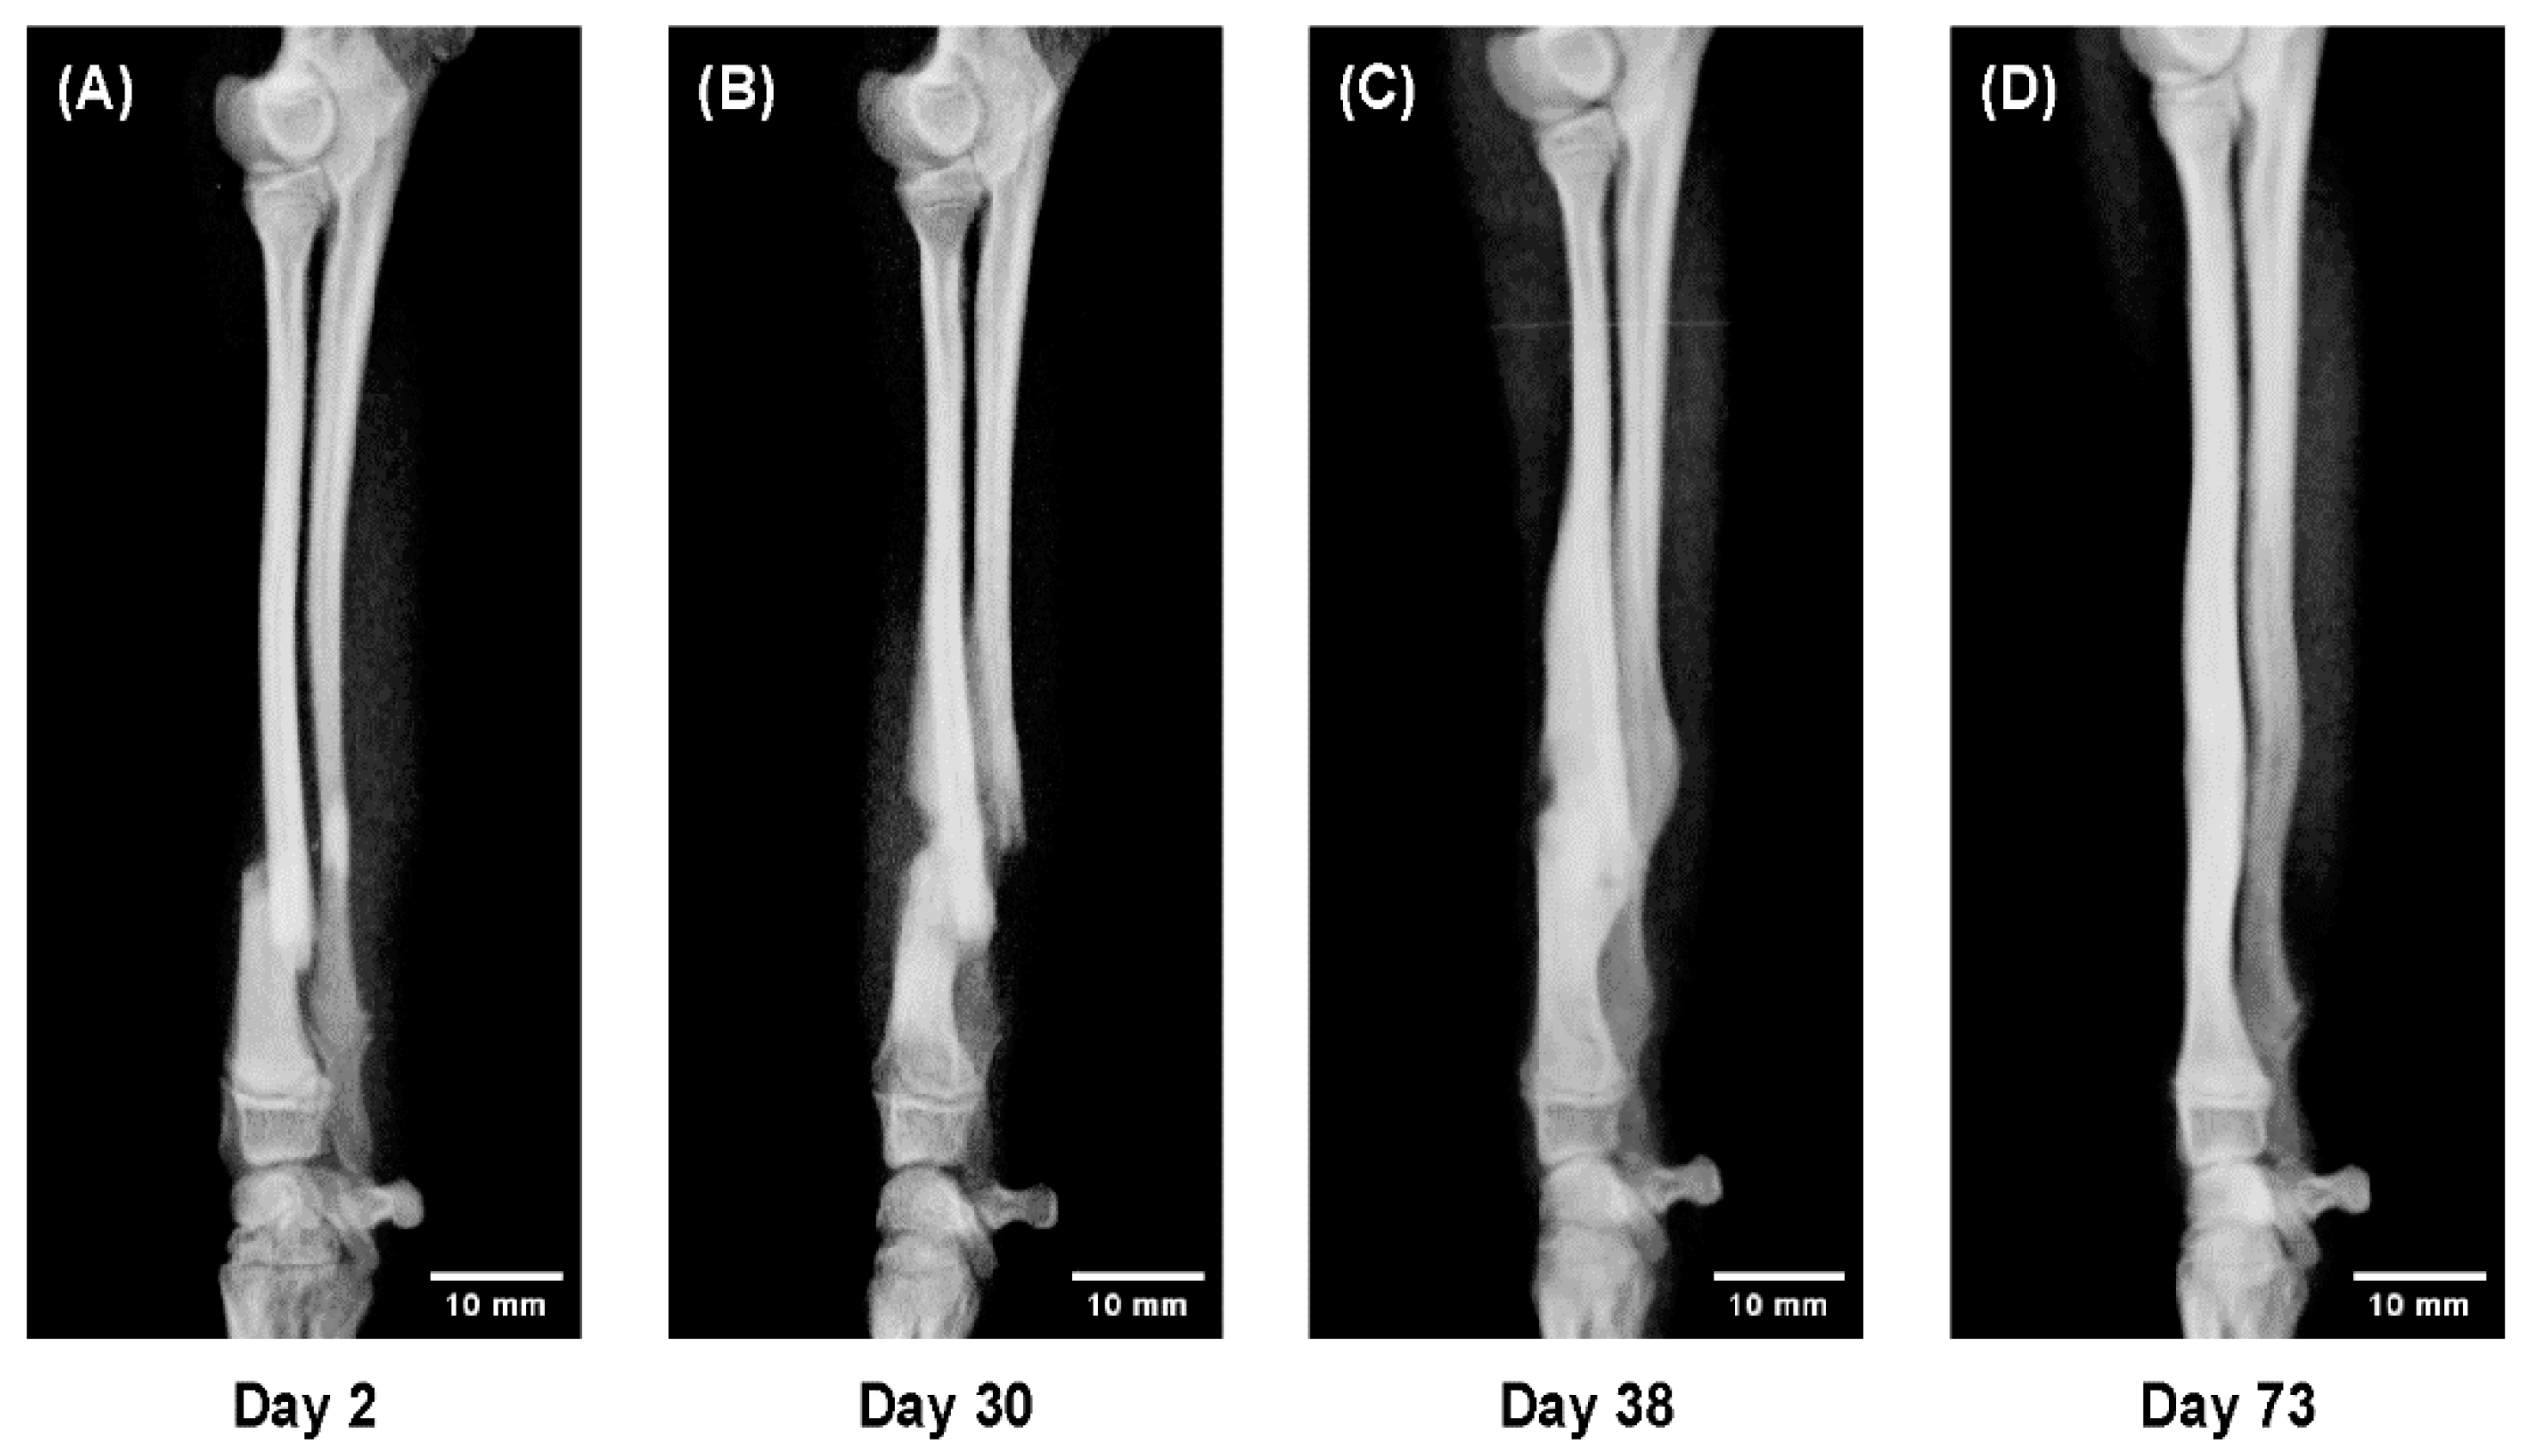

- A 5-month-old dog showing rapid callus proliferation (juvenile stage),

- Dogs aged 11 and 19 months showing reduced callus formation (adolescent stage), and

- Dogs aged 2 and 9 years showing stable but slower consolidation (adult to senior stage).

- A sequential radiographic series of a 5-month-old dog,

- Comparative observations between 11 and 19 months, and

- Between 2 and 9 years.

3.5. Radiographic Comparison by Age